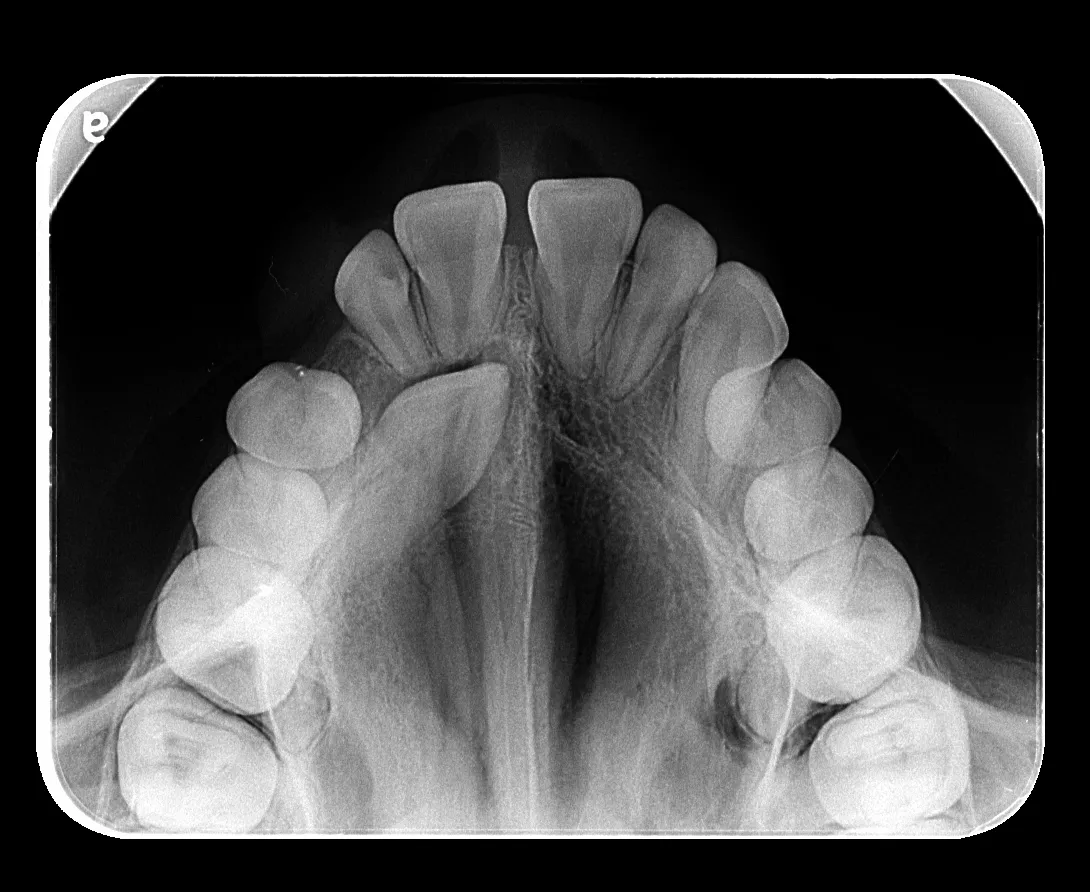

Radiografía Intraoral

La radiografía intraoral permite observar con gran detalle los dientes y las estructuras que los rodean. Es una herramienta fundamental para detectar caries, infecciones, fracturas, alteraciones en la raíz dental o en el hueso de soporte.